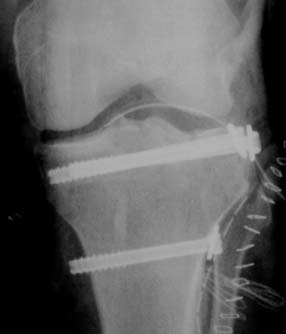

In hospital broken bone labeled Bruchstele Shin fixed with 3 screws Looking into the knee by arthroscope during surgical treatment

After exactly one half-year of untroubled riding pleasure it happens: I have an accident with my idiot-proof senior-citizen-vehicle! Suddenly my daily routine changes drastically: ambulance, university hospital, X-ray (diagnosis: long break in the tibia-plateau, the shin), a cast, knee-puncture, operation (bones fixed back in place with three screws), rehabilitation exercises and laboriously learning to walk again with crutches. A total of 12 days in the hospital and then at first twelve weeks of not being allowed to put more than 10 kg on the leg, otherwise the bones will break again and the whole painful routine will start from the beginning.